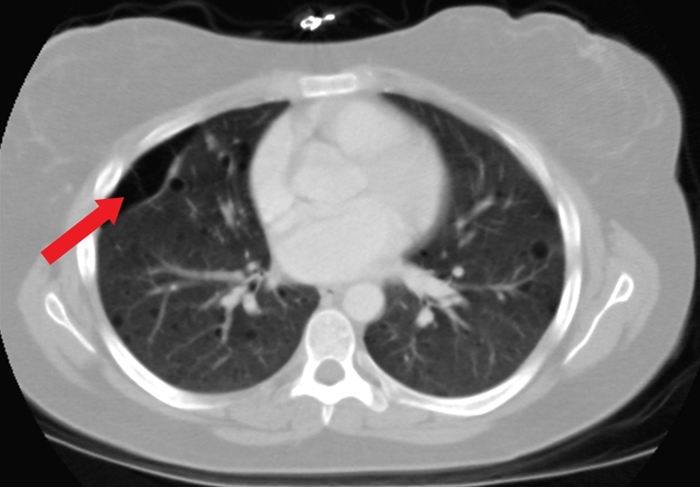

Secondary Spontaneous Pneumo

This patient with chronic obstructive pulmonary disease (COPD) and acute-onset shortness of breath, hypoxia, and unilaterally decreased breath sounds likely has a secondary spontaneous pneumothorax (SSP). SSP occurs in patients with known lung disease (eg, COPD, cystic fibrosis). Other common manifestations include chest pain and hyper-resonance on percussion. Cigarette smoking markedly increases the risk of pneumothorax. Chronic destruction of alveolar sacs leads to the formation of large alveolar blebs (red arrow), which can eventually rupture and leak air into the pleural space.